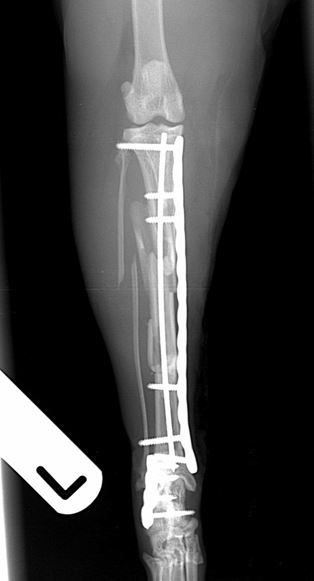

Six weeks post-operative lateral and craniocaudal radiographs         Six weeks post-operative lateral and craniocaudal radiographs

Fig. 3. Six weeks post-operative lateral and craniocaudal radiographs showing complete healing of the calcaneal fracture and excellent progression of healing of the tibial fracture